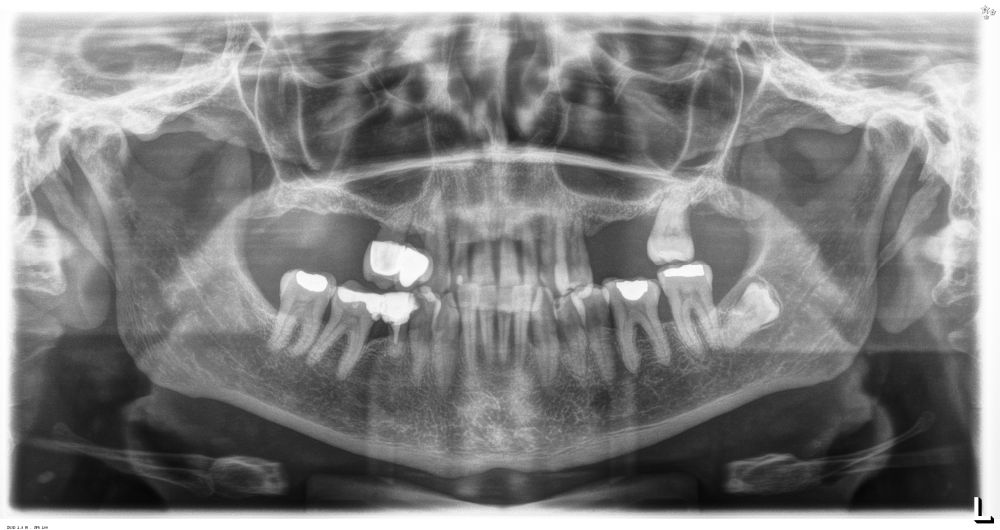

Presentamos el caso de una paciente femenina de 56 años de edad que acude a la consulta demandando un tratamiento con implantes dentales para reponer los dientes ausentes en ambos sectores posteriores maxilares. En ambos cuadrantes superiores, los molares se perdieron hace varios años. La paciente no se ha realizado la reposición de los mismos hasta ahora, ya que en otros centros consultados la propuesta terapéutica fue la de realizar injertos y regeneración ósea para poder ganar volumen óseo suficiente antes de colocar los implantes. La paciente busca otras alternativas menos invasivas y por ello acude a la visita. En las imágenes intraorales se observa la falta de los molares en los sectores posteriores maxilares con excepción del 27, que actualmente tiene un compromiso periodontal importante (Figuras 1-4). El resto de dientes también se encuentran afectados por una enfermedad periodontal avanzada con pérdida ósea horizontal (Figura 5).

Como primer paso, se realiza un escaneado intraoral de la paciente, para poder generar un encerado virtual con las piezas que queremos rehabilitar con implantes (Figuras 6-8). Esto nos permite planificar con claridad el caso y desde el modelo tridimensional, generar los provisionales y las guías quirúrgicas basadas en la posición protésica, que desde el flujo digital pueden imprimirse (Figuras 9-14). Desde el encerado podemos además generar otras guías, en este caso radiológicas, con las que realizar el Cone-Beam Computed Tomography (CBCT) de planificación. Con esta información tenemos en el mismo estudio radiológico la fusión de nuestra planificación quirúrgica y la posición real de la prótesis adaptada a la oclusión, muy útil para generar una planificación que contempla todos los parámetros. En este caso, se planifican implantes cortos de 6,5 mm en el primer cuadrante, de morfología Core-Xâ, para lograr una correcta estabilidad primaria en un tipo óseo IV como vemos en el corte seccional (Figuras 15 y 16). En el segundo cuadrante, con similares características, planificamos implantes de 6,5 y 5,5 mm de longitud (Figuras 17 y 18).